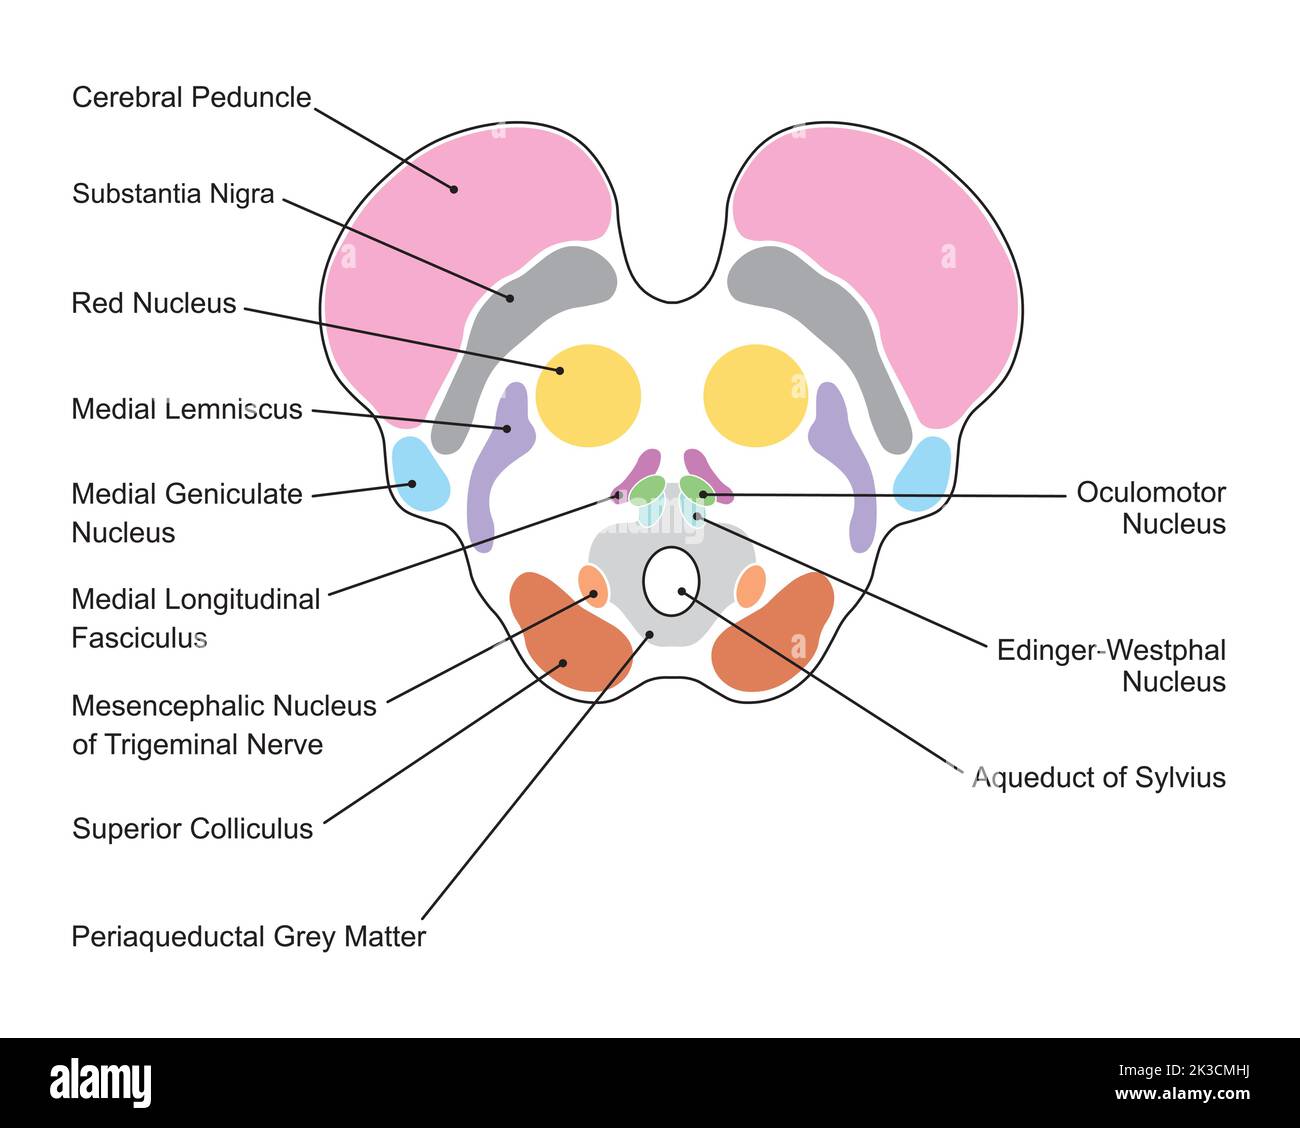

RF2K3CMNG–Progettazione scientifica dell'anatomia del midbrain. Sezione assiale a livello del collicolo superiore. Simboli colorati. Illustrazione vettoriale.

RF2K3CMHJ–Progettazione scientifica dell'anatomia del midbrain. Sezione assiale a livello del collicolo superiore. Simboli colorati. Illustrazione vettoriale.